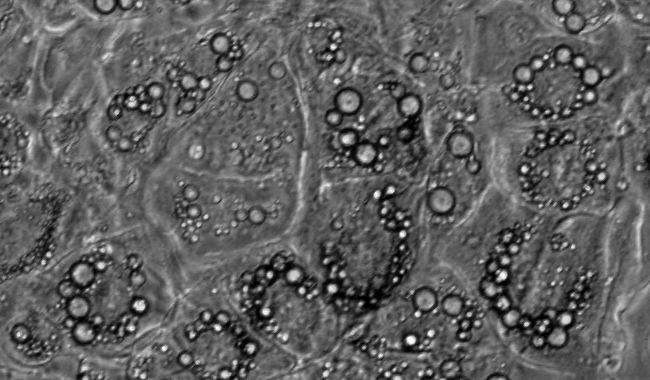

脂滴計(jì)數(shù)圖像分析

脂滴是調(diào)節(jié)中性脂質(zhì)儲(chǔ)存的基礎(chǔ),可以根據(jù)脂滴研究代謝的需求。但它們不僅是能量庫(kù),因?yàn)檫@種動(dòng)態(tài)的細(xì)胞器是許多生物過(guò)程的一部分,如細(xì)胞能量平衡和脂質(zhì)代謝。脂滴法在代謝性疾病的研究,如肥胖、糖尿病和動(dòng)脈粥樣硬化有重要的作用。

脂滴個(gè)數(shù)

脂滴覆蓋面積

平均覆蓋面積

區(qū)間分布

單個(gè)細(xì)胞的脂滴個(gè)數(shù)和覆蓋面積